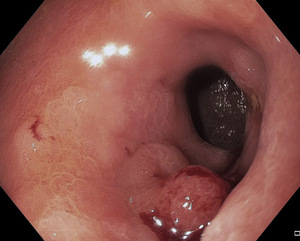

Wczesny rak przewodu pokarmowego definiowany jest jako nowotwór złośliwy pochodzenia nabłonkowego nieprzekraczający błony podśluzowej, bez cech naciekania błony mięśniowej właściwej. W przypadku wczesnego raka przełyku warunkiem rozpoznania jest wykluczenie obecności przerzutów do okolicznych węzłów chłonnych. Dokładność przedoperacyjnej oceny głębokości nacieku wczesnego raka oceniana jest na 70-95 proc. Wczesny rak może być widoczny jedynie jako zmiana zabarwienia błony śluzowej – częściej w postaci zaczerwienienia lub rzadziej – zblednięcia powierzchni. Szczególnie dotyczy to niewielkich zmian, trudnych do wykrycia w rutynowym badaniu (ryc.1). W przypadku znalezienia podejrzanej zmiany wskazane jest stosowanie barwień (płynem Lugola do nabłonka płaskiego lub indygokarminem albo błękitem metylenowym do nabłonka gruczołowego). Nowoczesne endoskopy wyposażone są w systemy powiększenia obrazu oraz systemy barwień elektronicznych oparte na oglądaniu zmian po podświetleniu ich wąską wiązką światła – (narrow band imaging NBI)(ryc. 2, 3).[2] Daje to możliwość dobrego uwidocznienia struktury powierzchni zmiany, jej granic oraz oceny rysunku naczyniowego, a co za tym idzie – wyboru optymalnego miejsca do pobrania wycinków. Tak precyzyjna ocena endoskopowa pozwala z ogromną dozą prawdopodobieństwa postawić jednoznaczne rozpoznanie, dlatego zwana jest też biopsją optyczną.[3] Tak więc decydujące znaczenie ma obraz endoskopowy: wielkość i kształt zmiany, jej typ makroskopowy określany wg klasyfikacji japońskich (ryc. 4).[4]

Makroskopowo wyróżnia się następujące typy wczesnego raka przewodu pokarmowego:

Typ I – wyniosły

Typ II – powierzchowny

IIa – powierzchowny uniesiony

IIb – powierzchowny płaski

IIc – powierzchowny obniżony

Typ III – zapadnięty